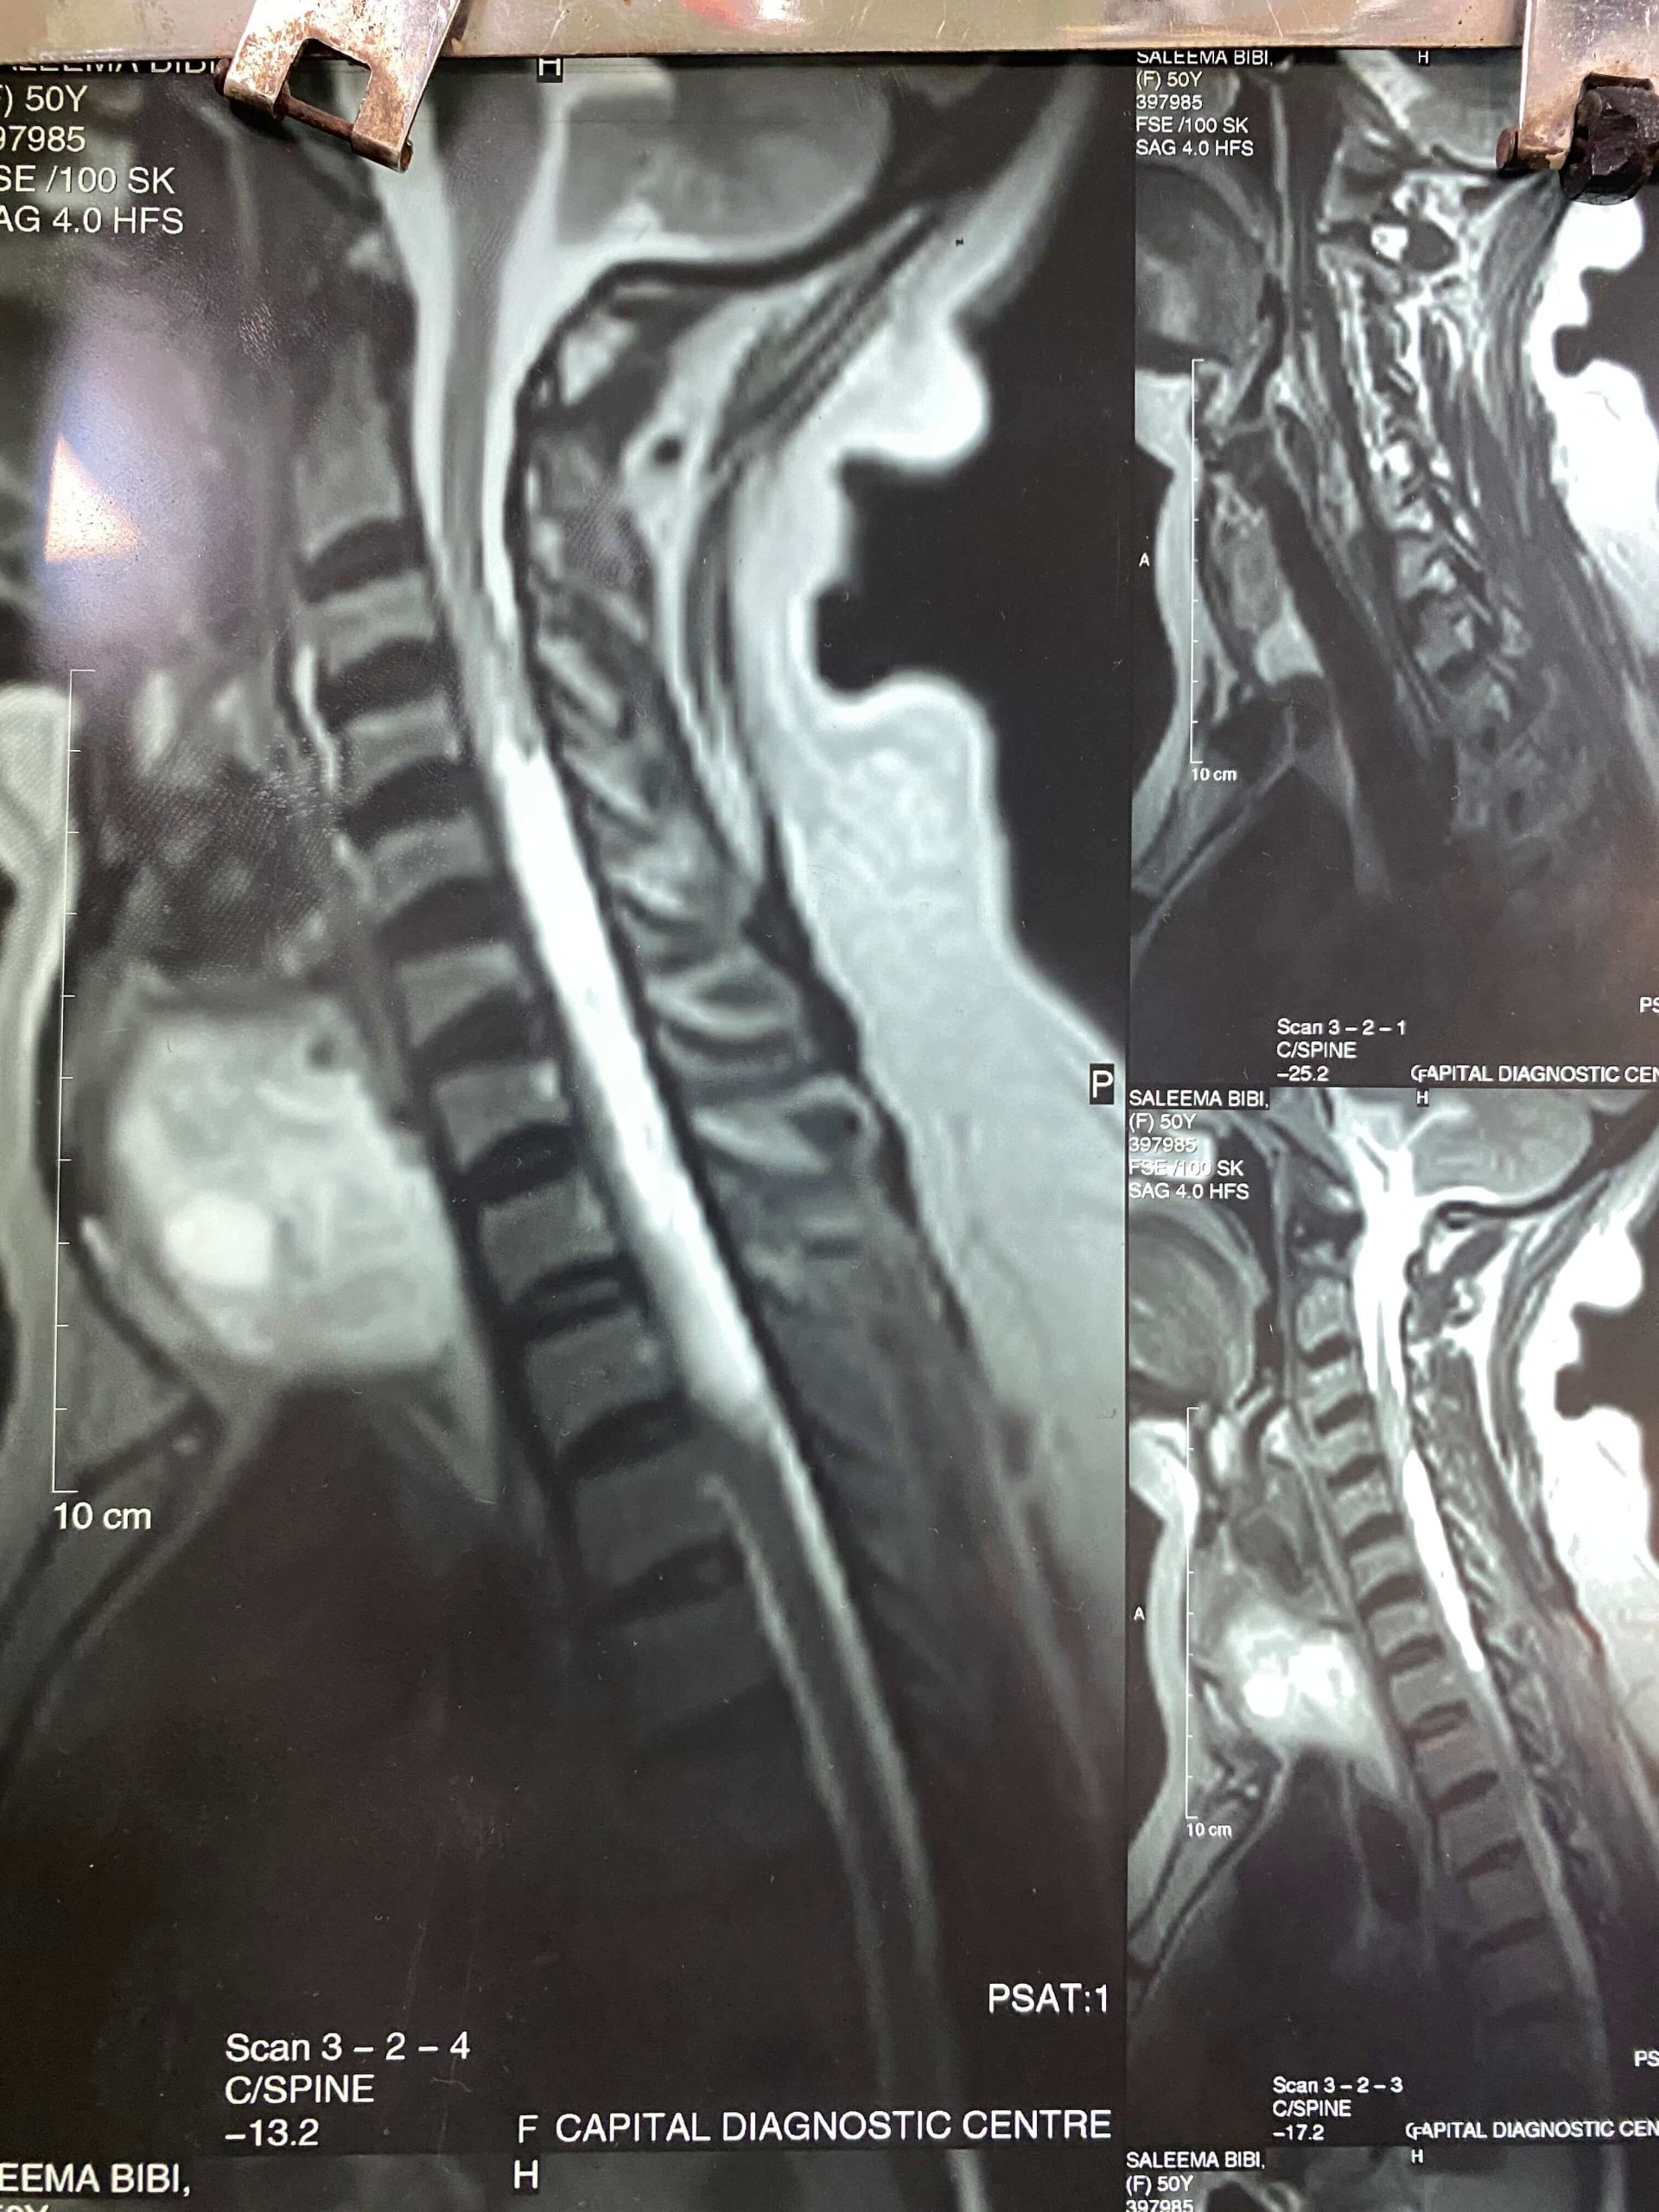

A spinal tumor is an uncontrolled growth of cells in the spine. These tumors can either originate in the spine (primary tumors) or spread to the spine from other parts of the body (secondary or metastatic tumors). They can be benign (non-cancerous) or malignant (cancerous).

The symptoms of a spinal tumor can vary widely but may include back pain, numbness or weakness in the limbs, difficulty walking, loss of bowel or bladder control, and in severe cases, paralysis.